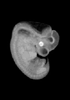

Carnegie Stage 16 (37 post-ovulatory days)

Most embryos at stage 16 are approximately 37 postovulatory days old and measure 11-14 mm in length. Distinguishing criteria for this stage include the external appearance of retinal pigment, the nasal pits face ventrally, pharyngeal arch 2 is more massive and conspicuous than arch 3, auricular bumps begin to appear, and the thigh, leg, and foot can be distinguished in the lower limb.

Photographs